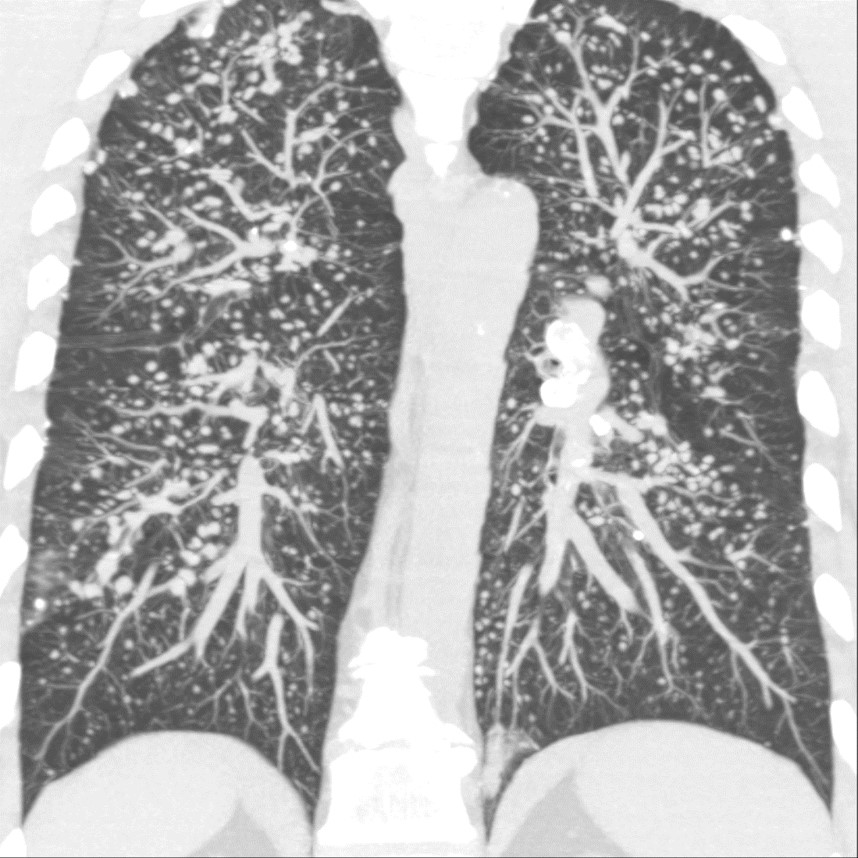

UIP: Example

UIP shows:3,6

- Subpleural and basal predominant distribution

- Honeycombing

- Traction bronchiectasis

The distribution of UIP is characteristically basal and peripheral, though often patchy.1,3,5,6

Image courtesy of and used with permission from Robert Suh, MD.

Honeycombing is critical for an HRCT diagnosis of UIP without surgical biopsy.1,3,5-7

In cases of UIP, ground-glass opacities (GGO) may be present but should be less extensive than the reticulation.1,3,6 Mediastinal lymphadenopathy may be present.3